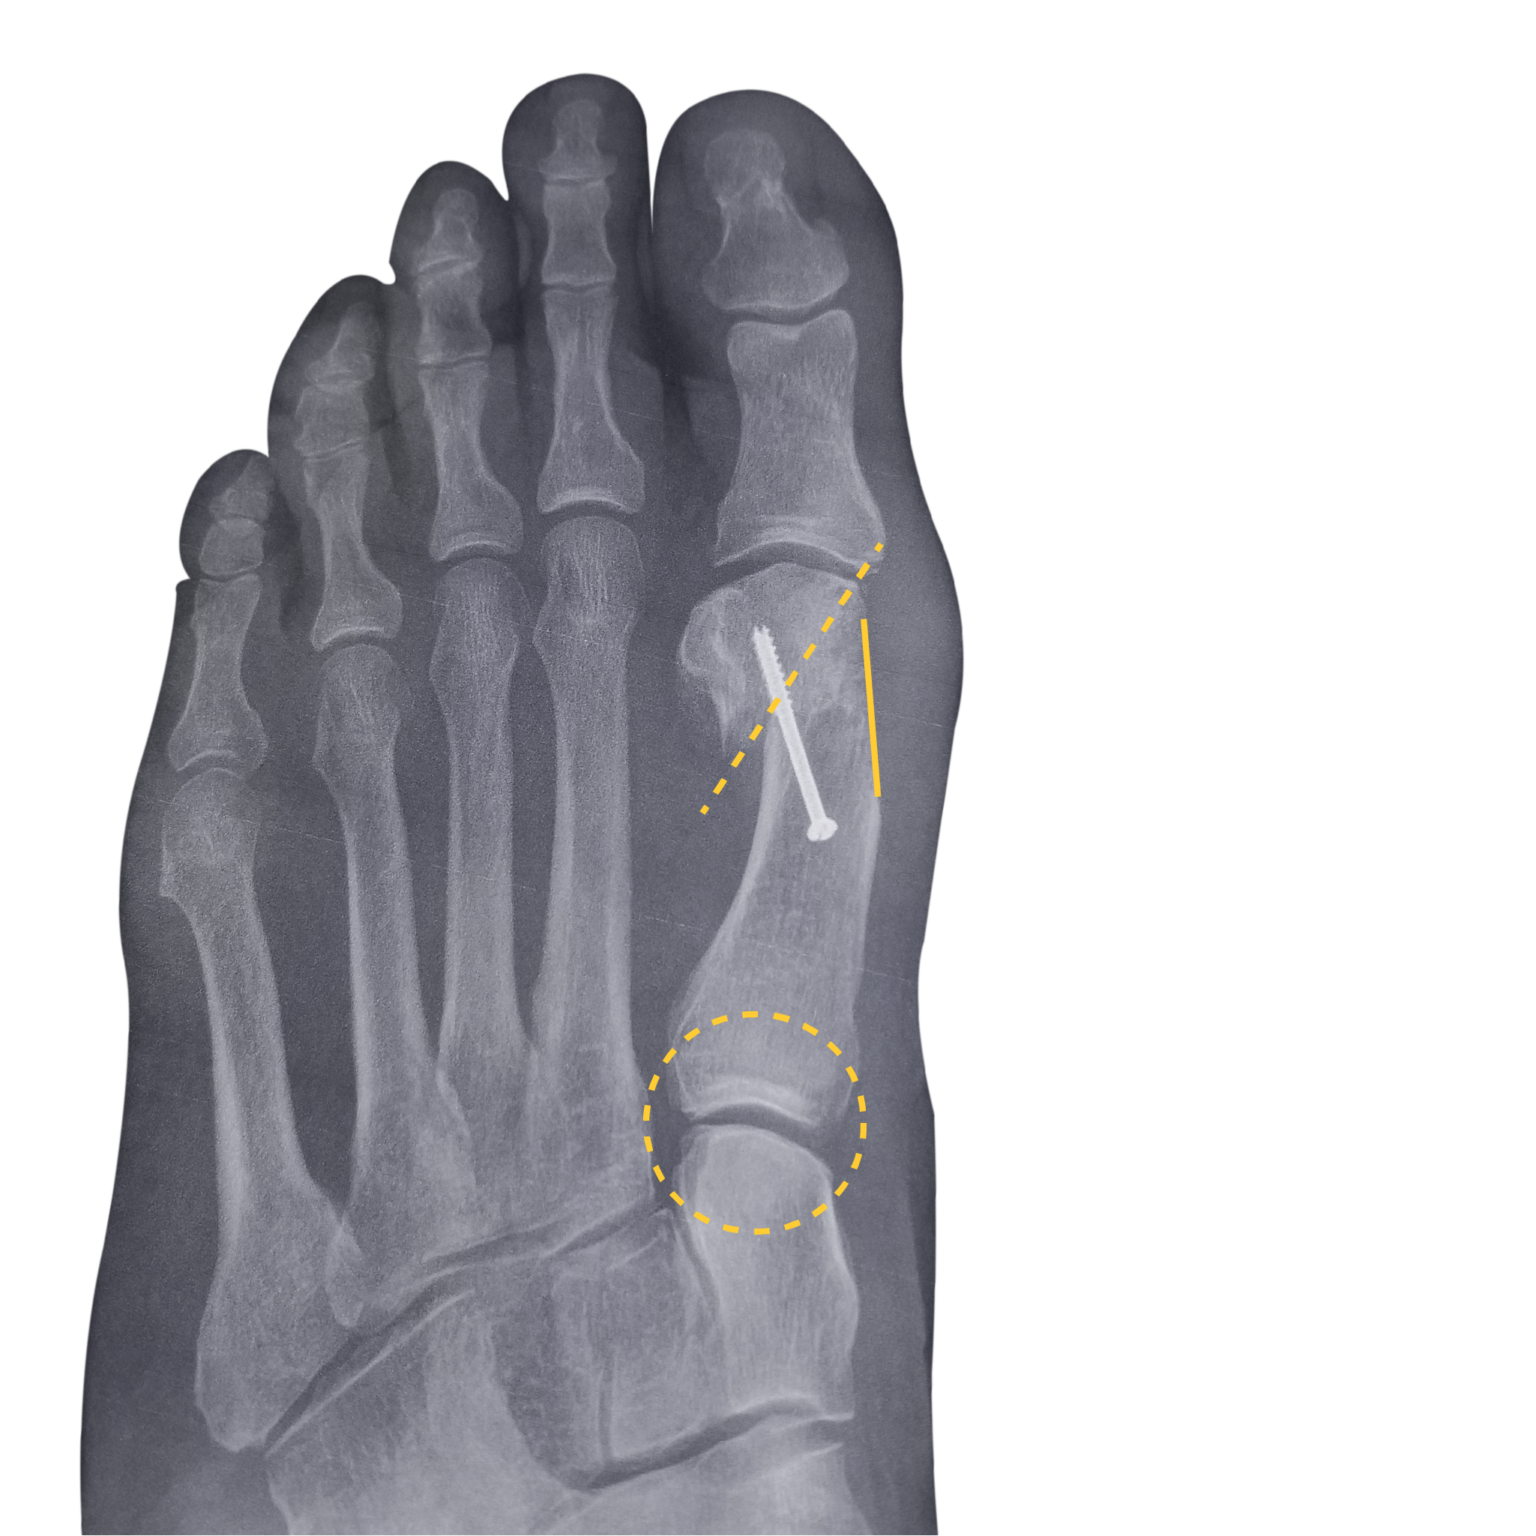

Minimally Invasive Bunion Surgery — Ortho San Antonio Bunion Surgery San Antonio the main objective of minimally invasive bunion surgery is to realign the joint, correct the deformity, and to relieve pain and discomfort with minimal. we are pioneers in minimally invasive surgery (mis) for bunions. if you have a severe bunion, or are in need of a foot specialist in san antonio, visit our office at 109 gallery. Bunion Surgery San Antonio.

Minimally Invasive Bunion Surgery in SA — Ortho San Antonio Bunion Surgery San Antonio if you have a severe bunion, or are in need of a foot specialist in san antonio, visit our office at 109 gallery circle, suite 119, san antonio, texas 78258, or. the main objective of minimally invasive bunion surgery is to realign the joint, correct the deformity, and to relieve pain and discomfort with minimal. san antonio. Bunion Surgery San Antonio.